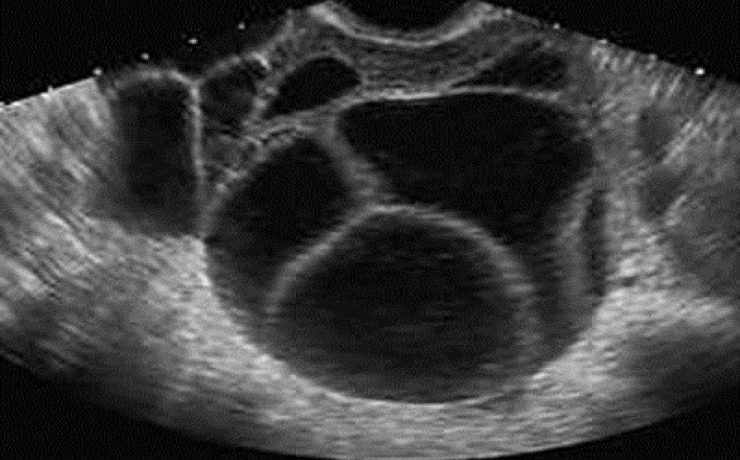

ÚTERO Y OVARIOS Al estudiar el hueco pélvico hay que tener en cuenta la anatomía del sistema reproductor femenino ya que partiendo de esto se podrán identificar anomalías en los mismos. Un punto importante para el estudio del hueco pélvico es utilizar la vejiga urinaria como ventana sónica, sin caer